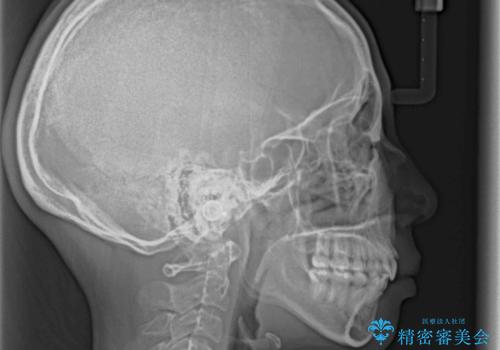

- 前歯のデコボコと上顎の前突感による口の閉じにくさを気にして来院された患者様です。

目立たない装置を希望されたので、上顎が裏側装置のハーフリンガルを選択し、上下左右の小臼歯(計4歯)を抜歯して矯正治療を行うこととしました。

治療期間の目安は2年半~3年間でしたが、咬み合わせにより上顎装置が頻繁に脱落してしまい、治療期間が長期化してしまいました。

期間はかかったものの、口元の張り出し感や歯のデコボコが解消され、患者様には大変満足していただけました。